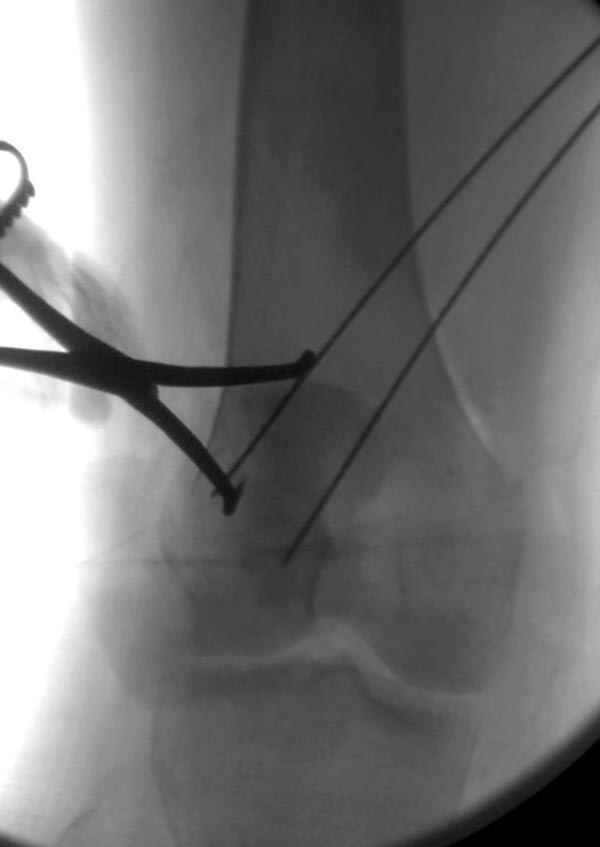

Сегодня досылаю остальные снимки, которые не прошли вчера. Как вчера писал, после фиксации перелома надколенника с дефектом кости и собственной связки, наложили ваккуум и наружный фиксатор. (снимки 4-9)

Внешний фиксатор держим около 6 недель, поэтому был выбран метод фиксации шурупами и еще линия перелома была диагональной, не было нужды в tension band technique, cannulated screws удобнее, провел спицы и по ним шурупы.

На слайдах (не четко обозначены бедро и голень): на бедре по наружно-передней поверхности, между вастус латералис и прямой головками, а на голени по передне-медиальной поверхности, желателен подбор длины резьбовой части стержня по ширине поперечника кости. На снимке: дистальное кольцо, метод проведения стержня через канюлю-проводник.